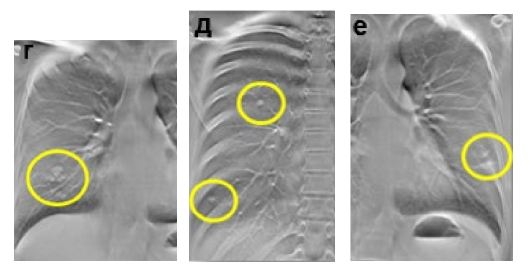

Метастатическое поражение лёгких: а – цифровая рентгенограмма ОГК в прямой проекции; б – цифровая рентгенограмма ОГК в правой боковой проекции; в, г, д, е – ТС ОГК.

Пациентка с диагнозом рак молочной железы. В средней доле правого лёгкого неотчётливо определяется округлой формы очаговая тень средней интенсивности с неровными контурами. На ТС в средней доле правого лёгкого выявляется группа очагов (желтый круг), дополнительно в обоих лёгких определяются множественные очаги неправильной формы, размерами до 10 мм (желтые круги). Заключение: Метастазы в обоих лёгких.